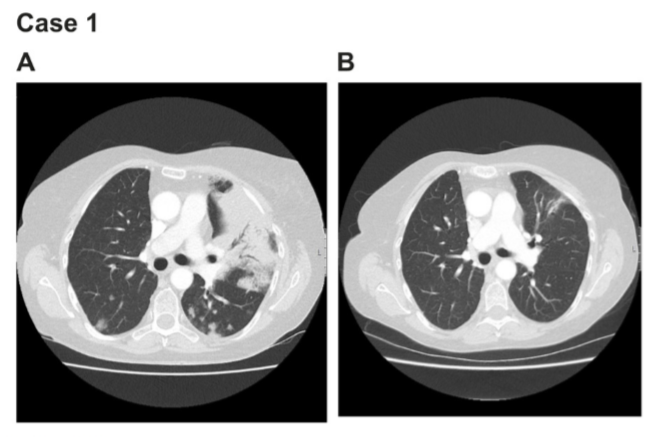

案例1

患者1为56岁女性,白人,从不吸烟,2004年被诊断为非粘液性肺腺癌。很遗憾,这位患者没有常见的KRAS、EGFR、ALK、ROS1、或ERRB2突变,无法选择对应的靶向治疗。

医生只能先后给患者进行了包括化疗在内的多种治疗尝试(超过14线的治疗),在医生和患者的努力下,每种治疗方案都有短时间的疗效。但患者最终还是不幸发生了左肺转移,医生采取了姑息疗法,先后用吉西他滨和培美曲塞控制住病情。

但随后的治疗中,患者对紫杉醇不耐受,患者出现咳嗽,发烧,缺氧和弥漫性肺纤维化等情况,病情难以控制。

命悬一线之下,患者于2015年2月尝试使用阿法替尼(30毫克/天),神奇的是,这名患者竟在短短的2.5个月使用时间里,迅速达到部分缓解(PR)。且PR时间长达24个月。

病情控制以后,医生继续给予培美曲塞和吉西他滨治疗,但病情出现持续进展。

考虑到患者之前使用阿法替尼的效果,在检测后发现患者有NRG1融合突变,因而重新引入阿法替尼(30毫克/天)治疗,患者咳嗽的症状明显减轻。随后提高剂量至40毫克/天,直至2018年8月患者显示进展,才停止阿法替尼使用。